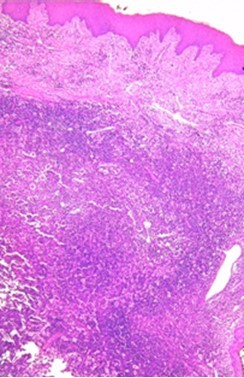

罗赛-多夫曼病(RDD)由 J Rosai 和 R F Dorfman 于 1969 年首次描述,是一种病因不明的良性、自限性组织细胞增生症。它通常出现在生命的头二十年。最常见的临床表现是无痛性双侧颈淋巴结病,伴有发热、体重减轻和血沉增快。然而,无结节受累的 RDD 极其罕见,最常见的结节外部位是头颈部,主要累及鼻腔、咽部和副鼻窦。口腔部位的罗赛-多夫曼病偶见;据我们所知,文献中仅发现 17 例无淋巴结受累的口腔罗赛-多夫曼病。由于这些孤立的口腔表现非常罕见,因此需要对其临床和放射学方面进行更多的研究。本文旨在介绍一例罕见的无淋巴结受累的口腔罗赛-多夫曼病病例,详细介绍其临床和影像学表现,以及对我们的患者所采用的治疗策略。

First described by J Rosai and R F Dorfman in 1969, Rosai-Dorfman disease (RDD) is a benign, self-limiting histiocytosis of unknown etiology. It is usually seen in the first two decades of life. The most frequent clinical presentation is painless, bilateral cervical lymphadenopathy accompanied by fever, weight loss, and an elevated ESR. However, RDD without nodal involvement is extremely rare, and the most common extranodal location is the head and neck region, mainly affecting the nasal cavity, pharynx, and paranasal sinuses. Oral location of RDD is occasional; according to our knowledge, only 17 cases of oral Rosai-Dorfman disease without lymph node involvement have been found in the literature. Because of the rarity of these isolated oral presentations, the clinical and radiological aspects need to be more studied. This article aims to present a rare case of oral Rosai-Dorfman disease without nodal involvement, detail the clinical and radiological signs, and the treatment strategy used in our patient.